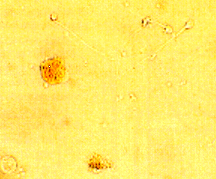

High white blood cell concentrations in semen, referred to as leucocytospermia, have been associated with genital tract infection and poor semen quality. The predominant white blood cell type is the polymorphonuclear granulocyte, normally comprising 50 – 80% of total seminal white blood cells. This subpopulation can be detected using a peroxidase test which visualizes the enzyme peroxidase in cells.